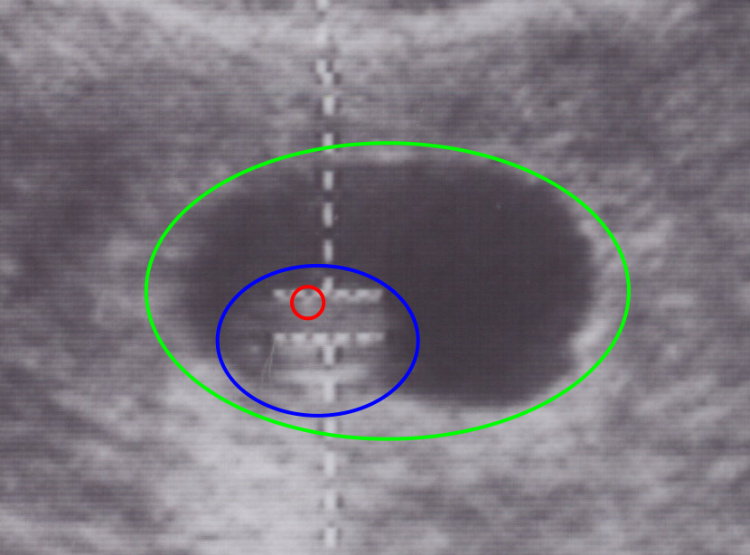

2007-05-12 八周 尺寸 - 1.87 cm

5/12 依然懷著忐忑不安的心情來到醫院 當聽到心跳時 心中一塊大石頭才放下來 換了家新醫院 這個醫生說了很多令人放心的話 例如寶寶很健康...等 不像之前的醫院 不斷恐嚇我們 沒看到胚胎時說可能子宮外孕 沒聽到心跳前可能是... sad 我不想說不好聽的話 所以就不寫出來了

紅色的圈圈就是心臟 聽到心跳時是安心 但是看到畫面上 心臟跳啊跳的時候 一股感動的暖流串過我整個身體 blushing 雖然整體看起來像蠶豆 但是到心臟一閃一閃時 我就真的感覺到我們的小孩存在了 不是圖片或者是透過儀器傳出來的聲音而已

藍色的圈圈就是我們家小小惡魔 laughing 圖片有點模糊 但是現場看真的像一顆蠶豆

綠色圈圈就是我們家小小惡魔第一間嬰兒房喔 俗稱羊水 好心的醫生用開心的口吻告訴我們 這就是他的房間喔!!!

第七周: 這時候的胚胎長約1.2釐米,形狀象蠶豆。

主要器官發展成形,這時候胚胎快要進入胎兒期,頭部仍像一團肉塊向尾部彎曲,四肢形狀較趨明顯,但呈蹼翼狀。而頭部器官如眼、耳、鼻、口皆已發育成形。另外心臟的四個房室構造形成。此時可透過腹部超音波看到心跳

附加檔案 小小惡魔-20070512-身高-web.jpg (56740 bytes) (下載次數: 5710) (小小惡魔第一張生活照)